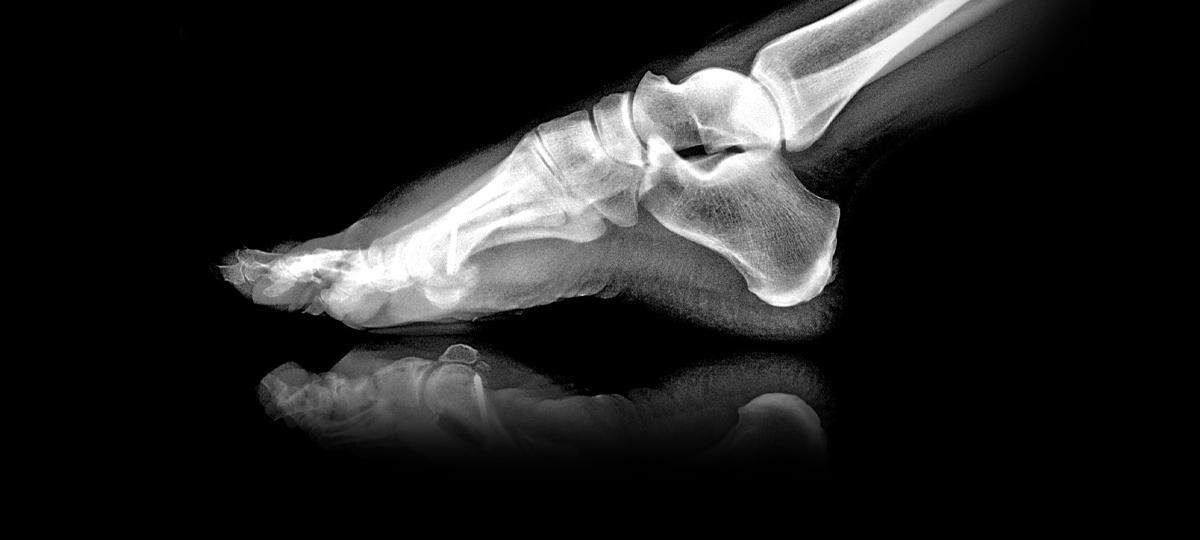

23.02.2019 14:21 Фото носит иллюстративный характер. Источник фото